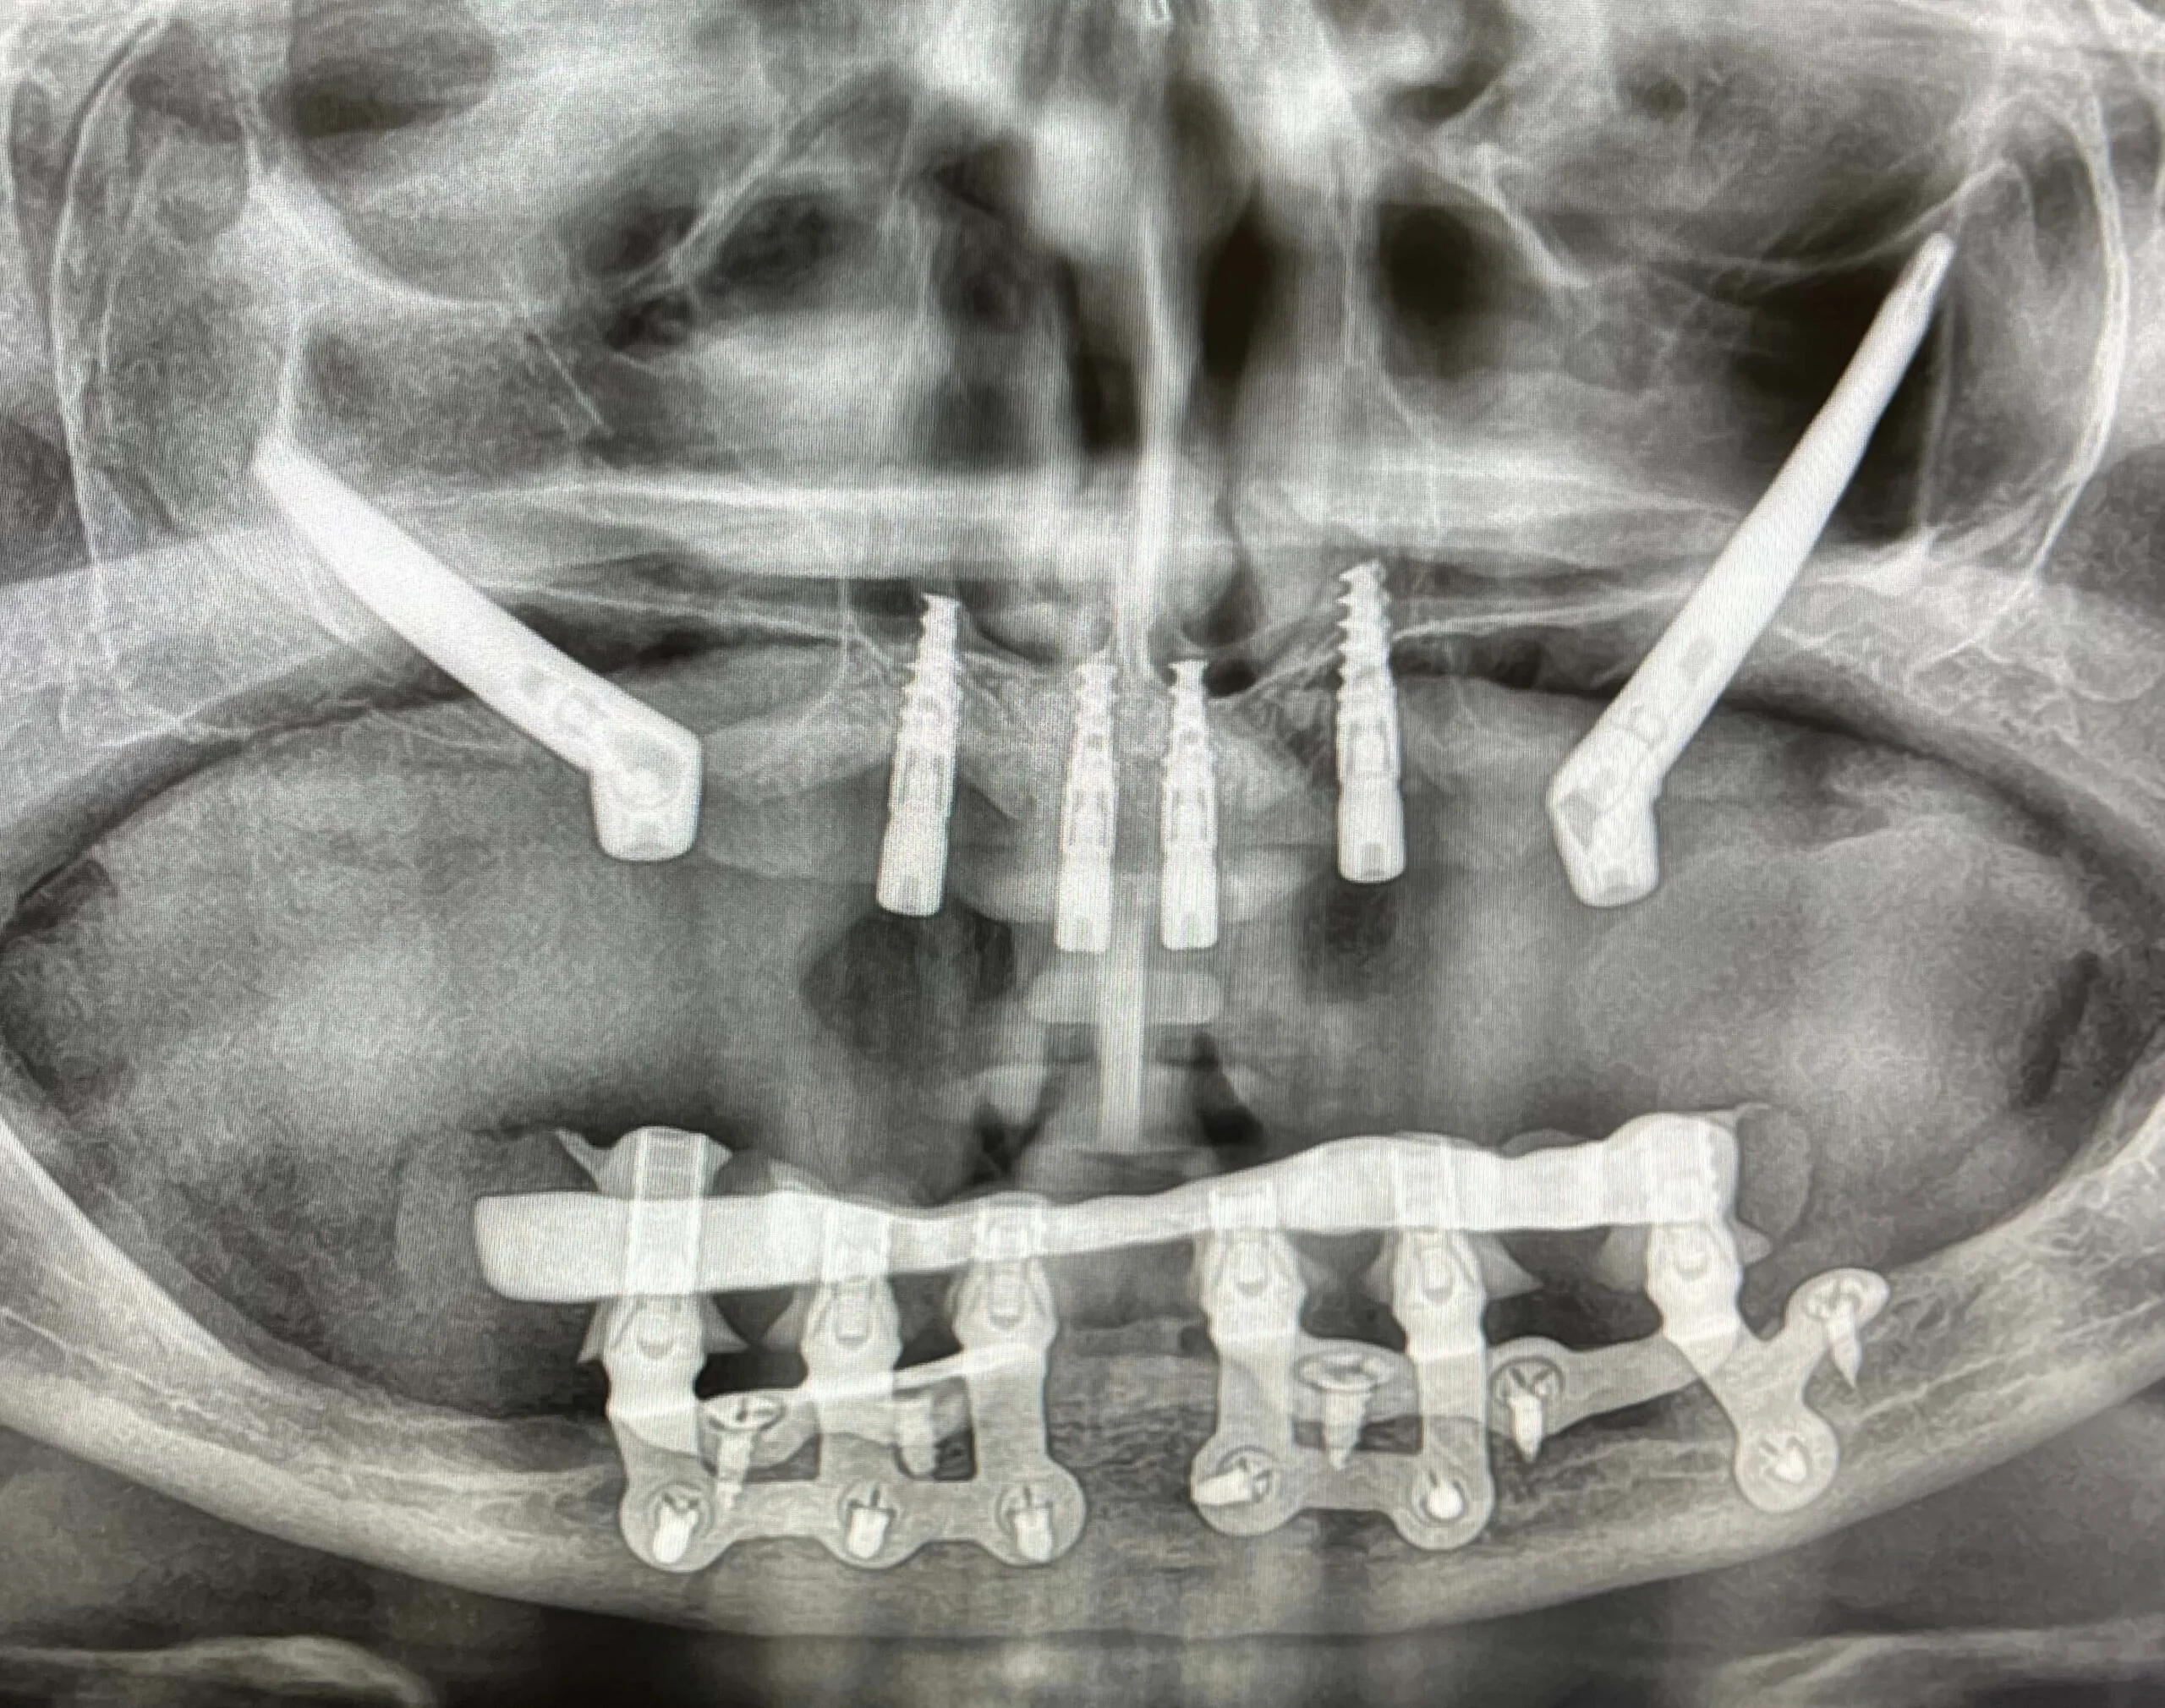

Pacjent 1

Dwa implanty zygomatyczne i 4 implanty klasyczne w szczęce, implanty podokostnowe w żuchwie.

Przykład implantologicznej przy całkowitym zaniku kości w żuchwie przy pomocy implantów podokostdnowych IUXTA 3D